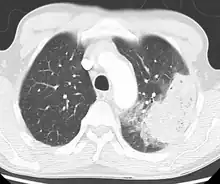

Cavitating pneumonia due to MRSA as seen on a CT scan

Bacteria are the most common cause of community-acquired pneumonia (CAP), with Streptococcus pneumoniae isolated in nearly 50% of cases.[34][35] Other commonly isolated bacteria include Haemophilus influenzae in 20%, Chlamydophila pneumoniae in 13%, and Mycoplasma pneumoniae in 3% of cases;[34] Staphylococcus aureus; Moraxella catarrhalis; and Legionella pneumophila.[18] A number of drug-resistant versions of the above infections are becoming more common, including drug-resistant Streptococcus pneumoniae (DRSP) and methicillin-resistant Staphylococcus aureus (MRSA).[21]

A CT scan can give additional information in indeterminate cases.[34] CT scans can also provide more details in those with an unclear chest radiograph (for example occult pneumonia in chronic obstructive pulmonary disease) and is able to exclude pulmonary embolism and fungal pneumonia and detecting lung abscess in those who are not responding to treatments.[33] However, CT scan is more expensive, has a higher dose of radiation, and cannot be done at bedside.[33]